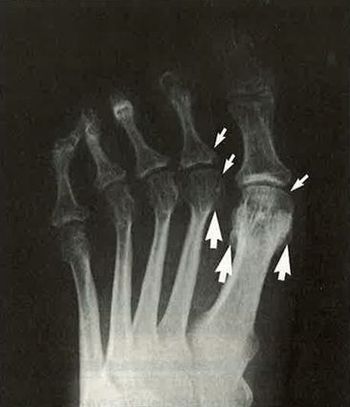

Psoriatic Arthritis